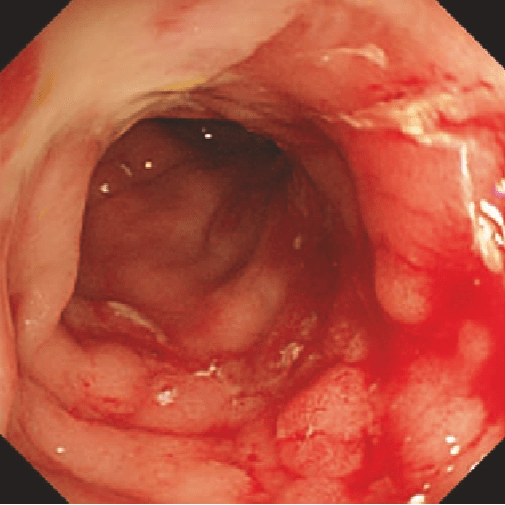

Диффузное воспаление с крупными язвами, «булыжной мостовой» И/ИЛИ сужением просвета

bolezn_krona.png

Rutgeerts i4